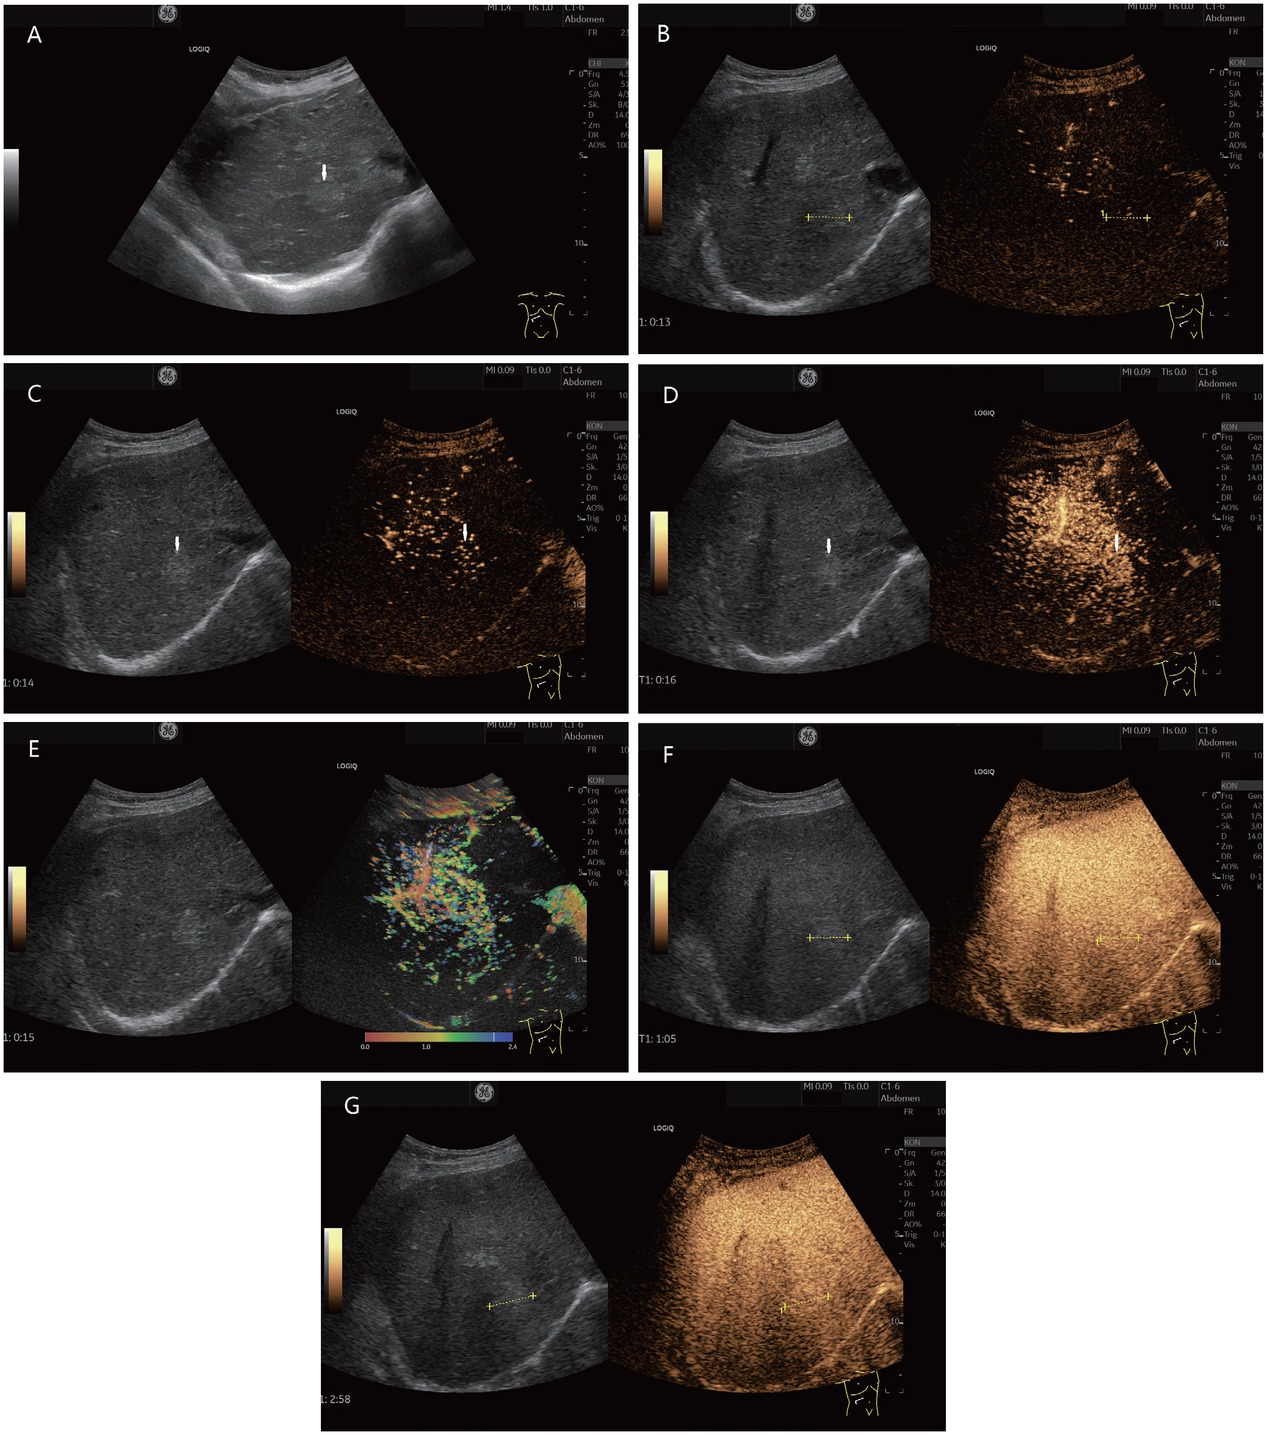

FNH or FNH-like lesion (histologically proven). In a 78-year-old female, ascites was diagnosed during gynecological examination. Further diagnosis revealed cirrhosis cardiac with a liver lesion. A 22-mm, slightly hyperechoic lesion was located in the right liver lobe adjacent to the inferior vena cava (in between markers and shown by arrows). This is shown on B-mode ultrasonography (A). A central vessel is visible on CEUS at the beginning of the arterial phase. The lesion is marked in the dual measurement (B). In the arterial phase, an evenly distributed contrast uptake is seen in the further course (C). The lesion is homogeneously enhanced. Increased contrast is conspicuous adjacent to the caudal part of the liver. Here, the contrast of a strong arterial vessel is visible (D). These phenomena are also seen in parametric imaging (E). In the portal venous phase (F) and late phase (G), the lesion remains hyperenhanced to the surrounding liver parenchyma. This was considered benign. On MRI, the lesion could not be clearly classified. Due to the hyperenhancement in the arterial phase and the diffusion disturbance in the MRI, the lesion remained suspicious. A sonographic guide biopsy was performed. The histology described an FNH. Follow-up over 6 months showed no change in findings. CEUS: contrast-enhanced ultrasonography; MRI: magnetic resonance imaging; FNH: Focal nodular hyperplasia.